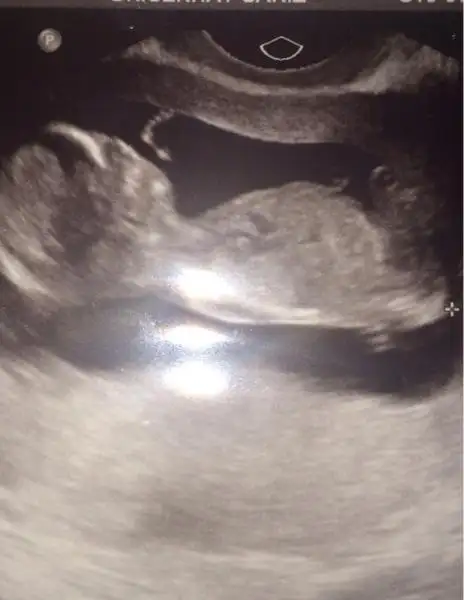

Eki Görüntüle 473829 bu bir erkek bebek genital nub cikintisi gayet yukarda

Eki Görüntüle 473831 simdi burada cikintilara bakin eger bel popo cizgisine paralel ise kiz

yok 30 derecelik bir aciyla yukari bakiyorsa erkek

Eki Görüntüle 473837 bu benim kizim cikinti gayet net ve ortada ve ben kizim diyooo

erkek bebekler

Eki Görüntüle 473852

Eki Görüntüle 473853